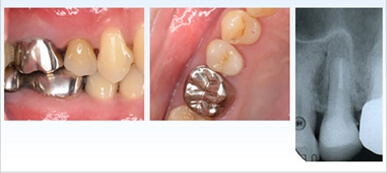

インプラント治療の症例

インプラント治療例その1(下顎奥歯にインプラント3本埋入、60歳代女性)

この症例のようにインプラント周囲炎を予防する為には審美性より清掃性、機能性優先をお勧めします。

| 治療内容 | インプラント治療(下顎奥歯にインプラント3本埋入) |

|---|---|

| 治療期間・回数 | 約3ケ月、約4~5回 |

| 治療費用 | ¥1,243,000 |

| 治療のデメリット | 歯に比べ感染に弱いので、徹底した口腔衛生管理が必須 保険適用外のため、自費診療となる |